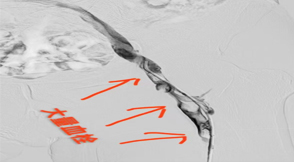

(圖片來(lái)源網(wǎng)絡(luò),如有侵權(quán)聯(lián)系刪除)“血栓、栓塞、纖維蛋白原”的命名人德國(guó)的RudolfVirchow(威爾蕭)教授于1856年提出血栓形成三...